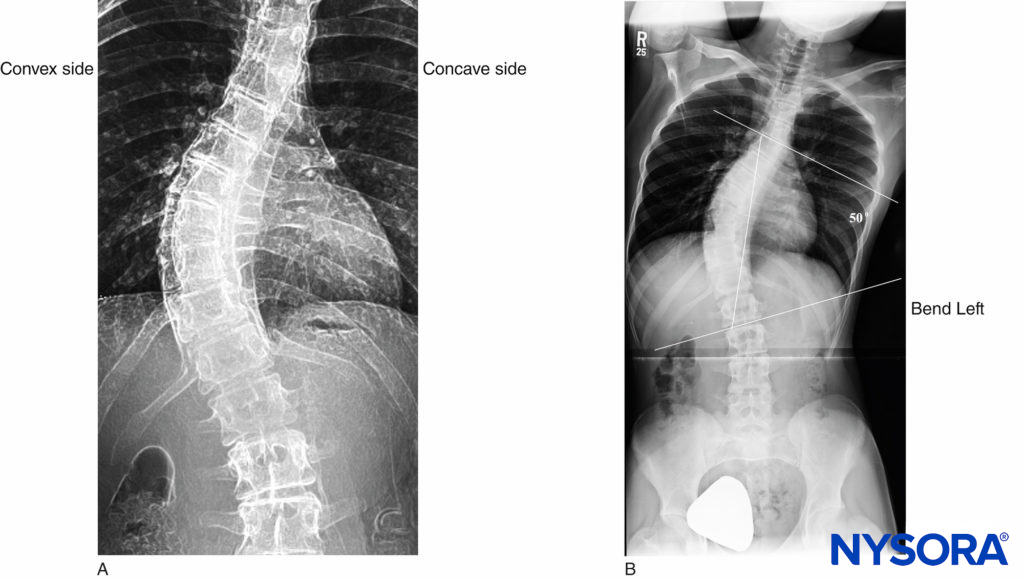

Adult scoliosis, in particular, is frequently encountered in older adults. In fact, Schwab et al demonstrated that scoliosis was present in 68% of an asymptomatic volunteer population older than 60 years of age. A thorough understanding of the scoliotic spine will aid in successfully performing central neuraxial block in this patient population. In the scoliotic spine, vertebral bodies are rotated toward the convexity of the curve, and their spinous processes face into the concavity of the curve (Figure 8).

The diagnosis of scoliosis is made when there is a Cobb angle of greater than 10° in the coronal plane of the spine in a skeletally mature patient. The Cobb angle, which is used to measure the magnitude of scoliosis, is formed between a line drawn parallel to the superior endplate of one vertebra above the curve deformity and a line drawn parallel to the inferior endplate of the vertebra one level below the curve deformity (Figure 8). In untreated patients, there is a strong linear relationship between the Cobb angle and the degree of vertebral rotation in both thoracic and lumbar curves, with maximum rotation occurring at the apex of the scoliotic curve. A compensatory curvature of the spine always occurs in the opposite direction of the scoliotic curve.

FIGURE 8. Adolescent scoliotic spine. A: S-shaped scoliosis of the thoracolumbar spine. B: Cobb angle of 50°.